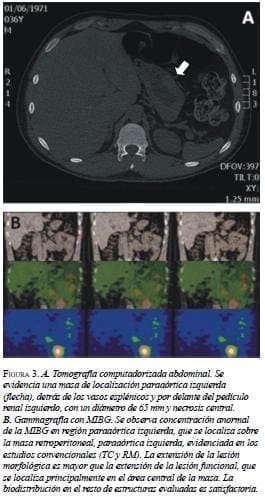

En agosto de 2008, reaparecieron los síntomas, acompañados de nuevas crisis hipertensivas, por lo cual se decidió determinar los niveles de ácido vanilmandélico (tabla 1) y practicar una TC, en la que se encontró una lesión residual de localización paraaórtica, detrás de los vasos esplénicos y por delante del pedículo renal izquierdo, con un diámetro de 65 mm y necrosis central (figura 3). A partir de este hallazgo se decidió programarlo nuevamente para cirugía. En el periodo posoperatorio, el electrocardiograma presentó inversión de la onda T en dos derivaciones y trastornos en la repolarización, sin síntomas asociados.